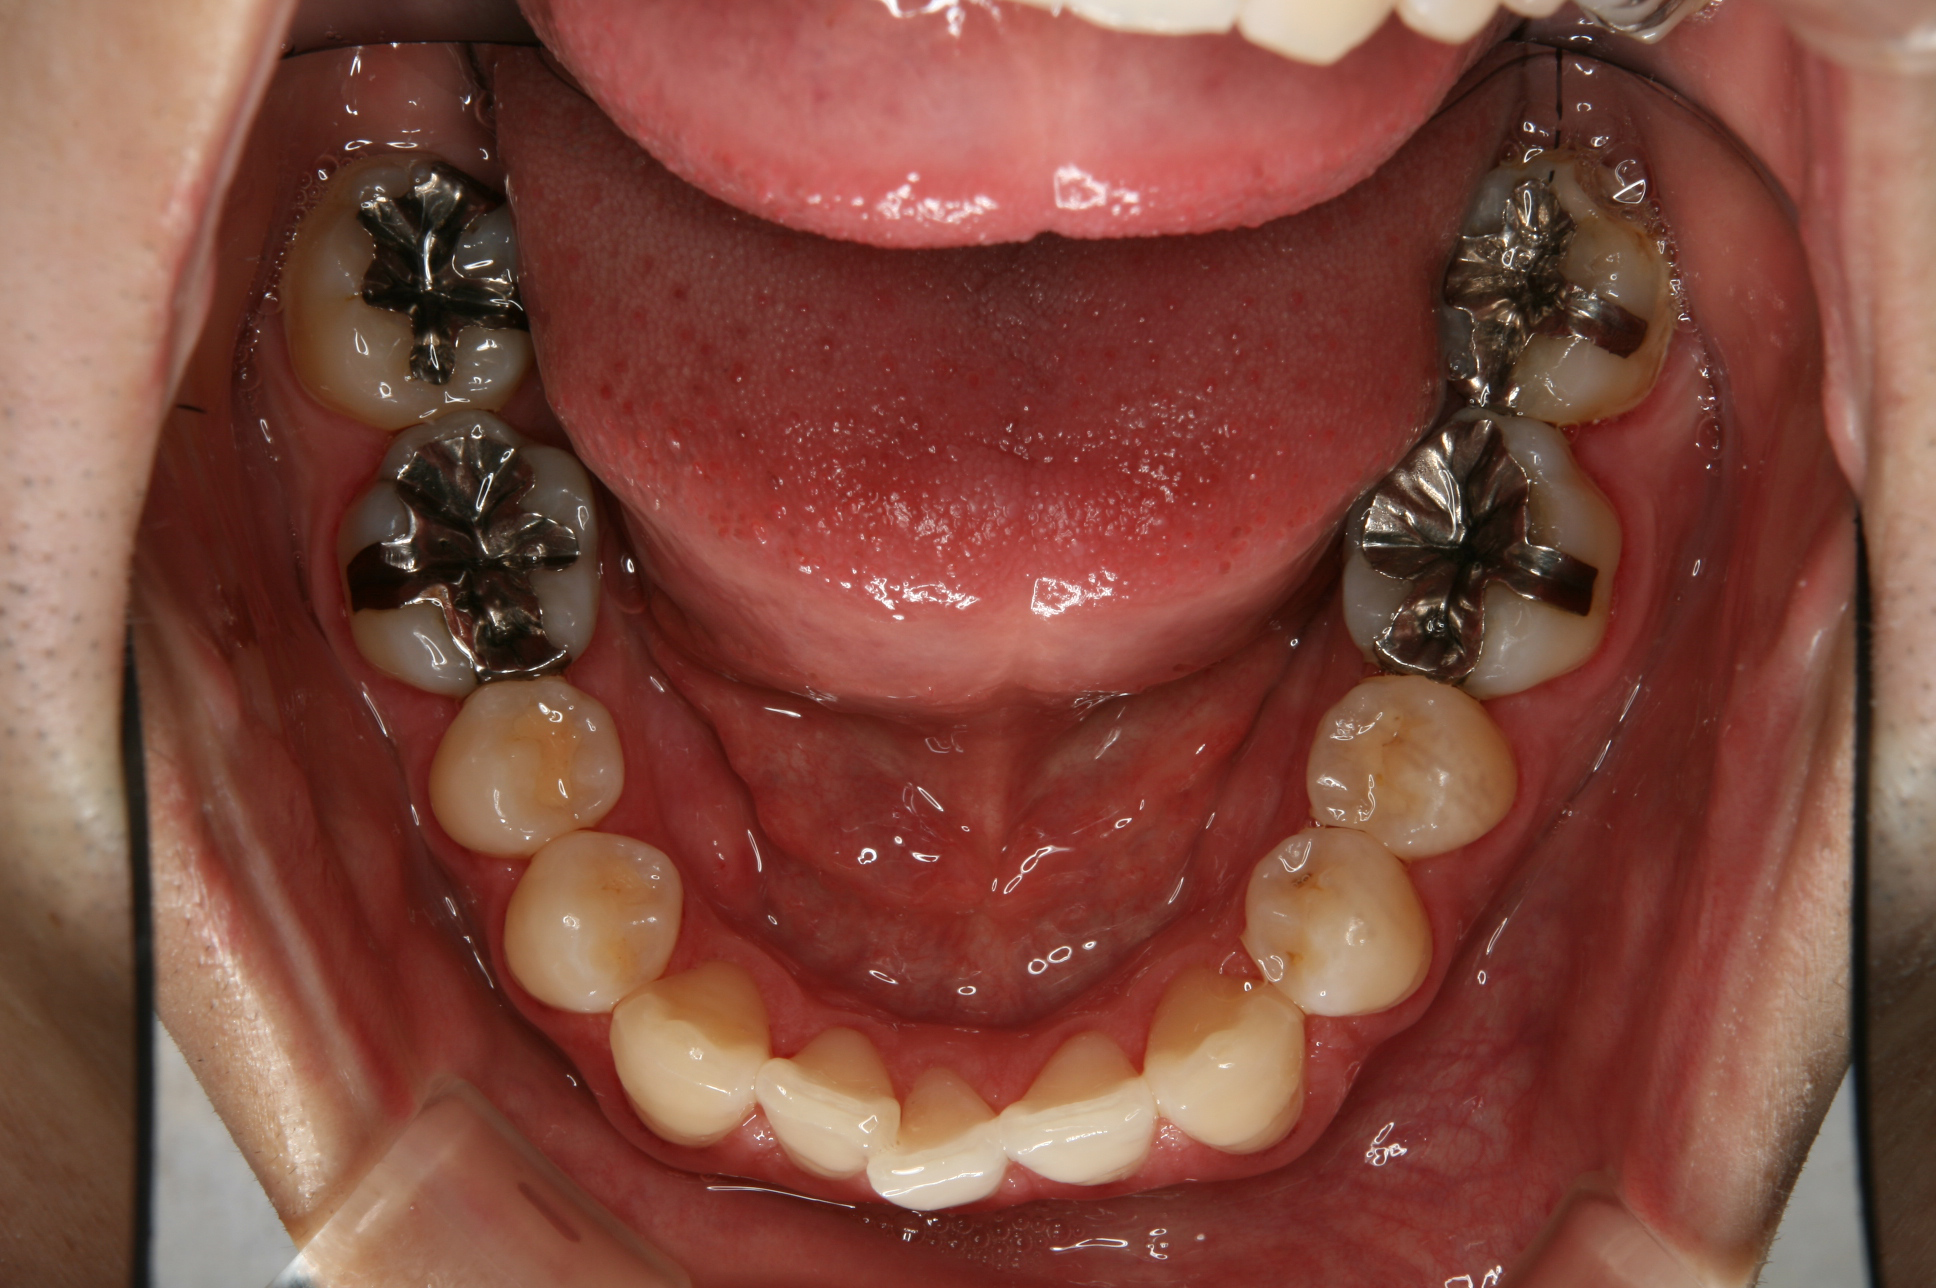

こちらは、以前私が行った審美修復の治療例です。

②治療前です。 ②ハイブリッドレジン修復後です。